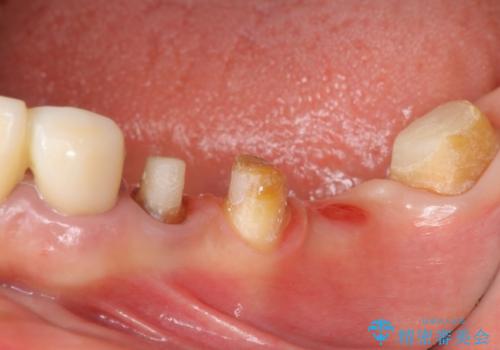

- 毎回食事のたびに食べかすがつまり、見た目も気になる銀歯のブリッジやりかえを希望され来院されました。

精度の高いジルコニアブリッジの製作に加え歯茎にぴったりとそわせたオベイトポンティック形態とすることで清掃性・審美性に優れたブリッジを製作します。